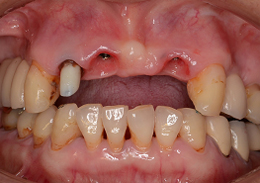

インプラントブリッジのジルコニアオールセラミックにて前歯部・審美領域の治療

- 主訴

- 事故で前歯を喪失、見た目と噛み合わせを治したい

- 治療内容

- 上顎前歯2本のインプラントと右上の天然歯を、同時に色調を合わせて修復を行なった

- 治療費用

- インプラントに関わる治療費:1,025,000円(税別)

- 治療期間

- 5ヶ月